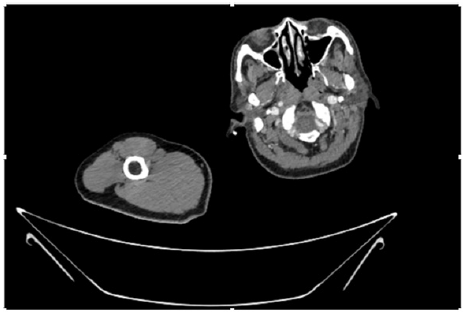

Figure 4: CT Angiogram at neck showing normal brachio-cephalic trunk, common carotid artery, and narrow right subclavian artery.

Figure 5: CT Angiogram at neck showing normal brachio-cephalic trunk, common carotid artery, and narrow right subclavian artery.

Figure 6: CT Angiogram at neck showing brachio-cephalic trunk, common carotid artery and narrow right subclavian artery.

Figure 7: CT Angiogram at neck showing brachio-cephalic trunk, common carotid artery and narrow right subclavian artery.

Figure 10: CT Angiogram at upper arm showing totally occluded right axillary artery; normal internal carotid artery and external carotid artery.